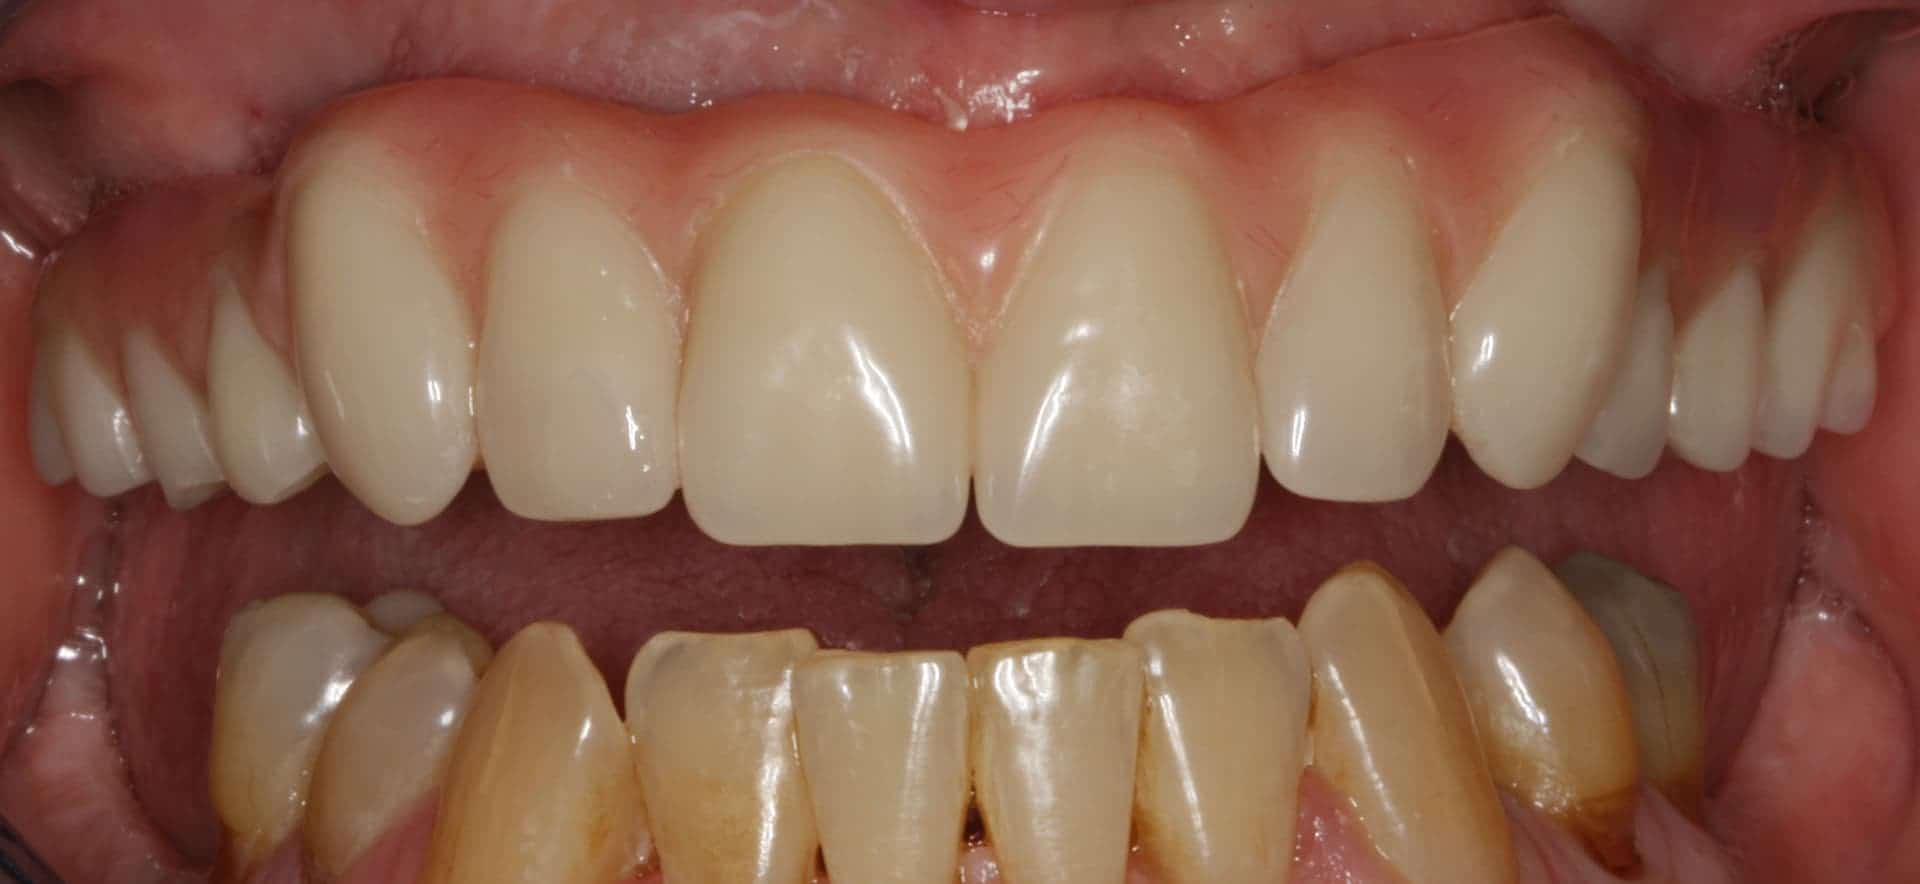

Before: Failed upper remaining teeth requiring removal. Patient elected to proceed with Phase I immediate complete denture therapy with the view toward phase II implant therapy.

After: Maxillary (upper), acrylic fused to metal, fixed (hybrid) screw-retained (retrievable) restoration supported by 6 titanium root form dental implants. The restoration is fixed, therefore only Dr. Leopardi can remove it for routine maintenance and hygiene, as needed. The patient cleans the fixed restoration as he does his natural lower teeth, with a tooth-brush, floss and water-pick. The outcome is improved function, mastication/diet, aesthetics and quality of life.